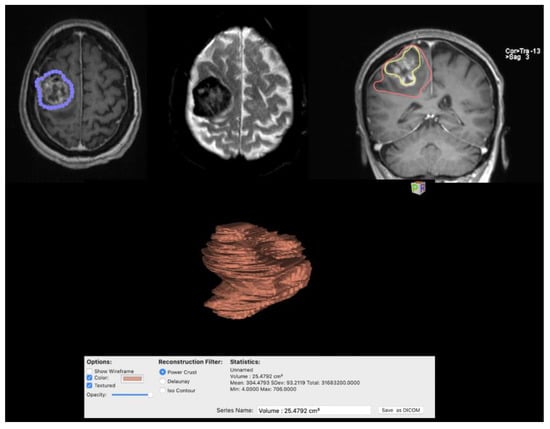

- Mandel, M.; Li, Y.; Figueiredo, E.G.; Teixeira, M.J.; Steinberg, G.K. Presurgical Planning with Open-Source Horos Software for Superficial Brain Arteriovenous Malformations. World Neurosurg. 2021, 157, 3–12. [Google Scholar] [CrossRef]